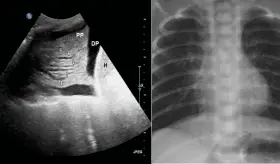

La hipertensión pulmonar, caracterizada por presión anormalmente alta en las arterias de los pulmones, requiere herramientas diagnósticas especializadas como el cateterismo cardíaco derecho para su confirmación.

Experto presentó los avances de una investigación que está transformando la comprensión del tratamiento de la hipertensión pulmonar en América Latina.